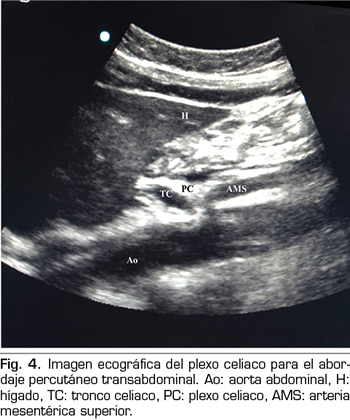

En los últimos años la ecografía ha ido ganando terreno a la fluoroscopia y al TAC en el manejo intervencionista del dolor. El primero en describir la técnica sobre el plexo celiaco fue Bhatnagar (31), pudiendo ser realizada percutáneamente en la cabecera del paciente y en decúbito supino, lo que da mayor comodidad tanto para el paciente como para el médico. Sin embargo, todavía no existen ensayos controlados y aleatorizados que comparen la neurólisis ecográfica abdominal del plexo celiaco frente al tratamiento sistémico opioide. La técnica se realiza utilizando una sonda convex (2-5 MHz), colocada inicialmente justo por debajo de la apófisis xifoides en el plano transversal, para identificar estructuras como hígado, estómago, intestino, venas portales, cava y aorta. Con la ayuda del Doppler, escaneamos caudalmente para identificar la bifurcación del tronco celiaco en las arterias hepática y esplénica, y más distalmente en la arteria mesentérica superior. Es entonces cuando giramos el transductor en el plano longitudinal, visualizando en la misma imagen la bifurcación de la aorta en el tronco celiaco y en la arteria mesentérica superior con el plexo celiaco rodeando estas estructuras. El abordaje se realiza en plano, transabdominal, atravesando el hígado o el estómago, siempre y cuando no haya grandes vasos interfiriendo el recorrido de la aguja (Figura 4).